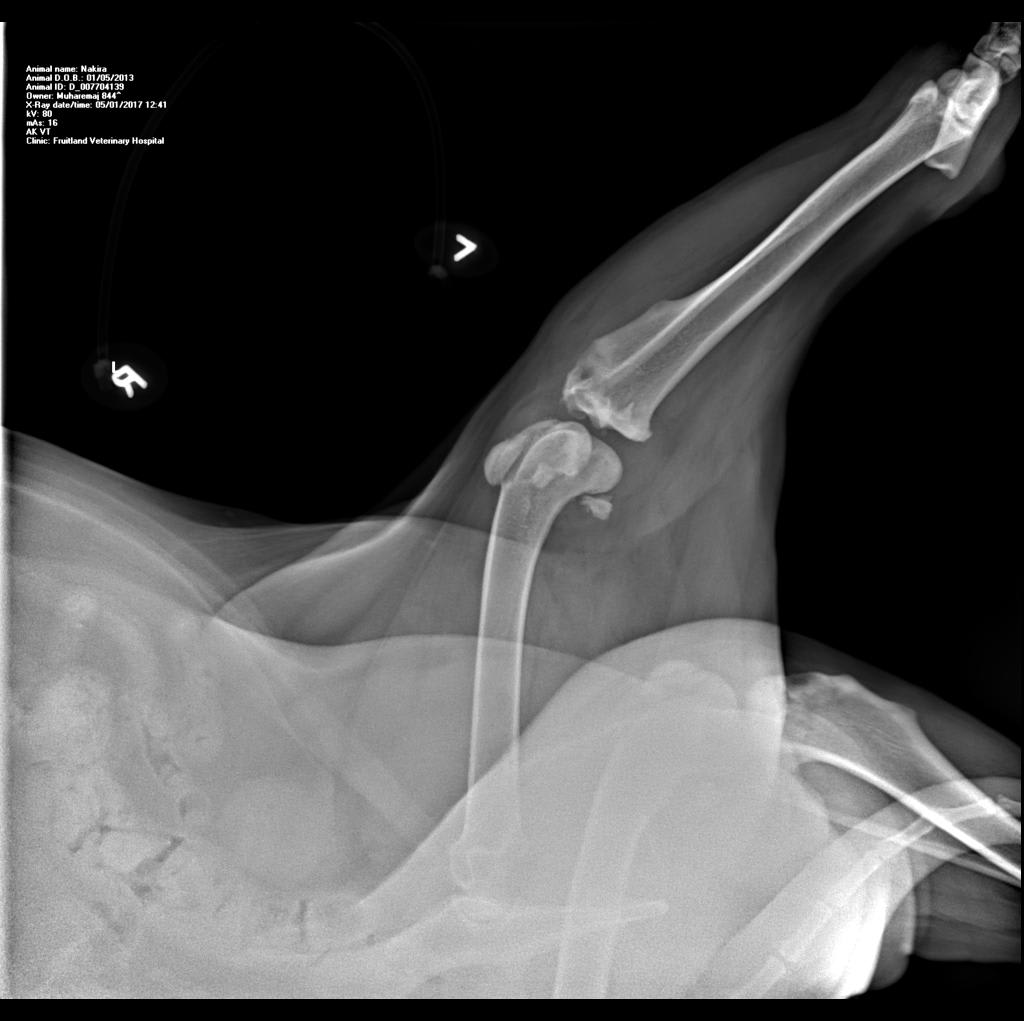

Hello there, I am looking for an expert HONEST opinion about my dog's knee condition...she is only 4 years old, and can barely walk (hind legs). A mastiff-bulldog mix, cca 130 lbs, ( on a special vet diet) spayed female. Motility problems started cca 18 months ago. I am attaching 3 x-rays. Is this a progressive illness and what is your recommendation (no surgeries). Thank you.